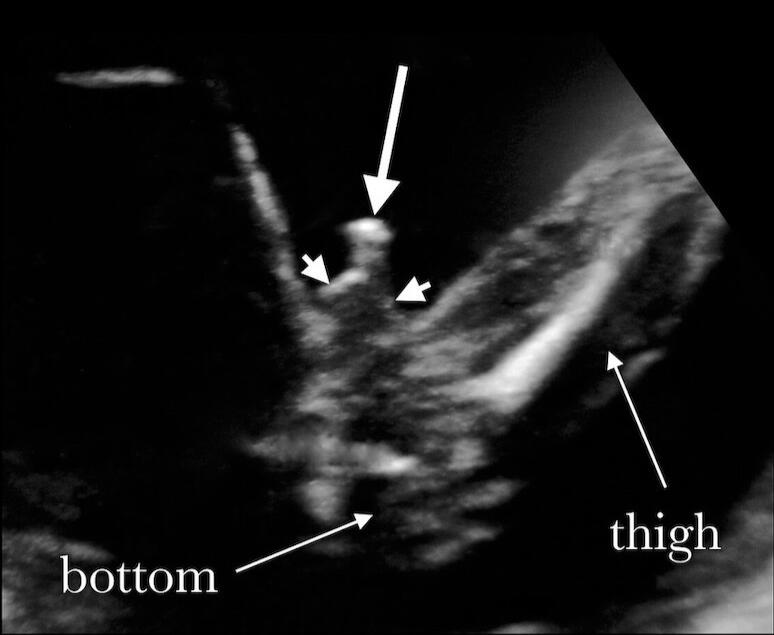

An image tutorial on how to pick apart gender differences from Week 14 through Week 38.